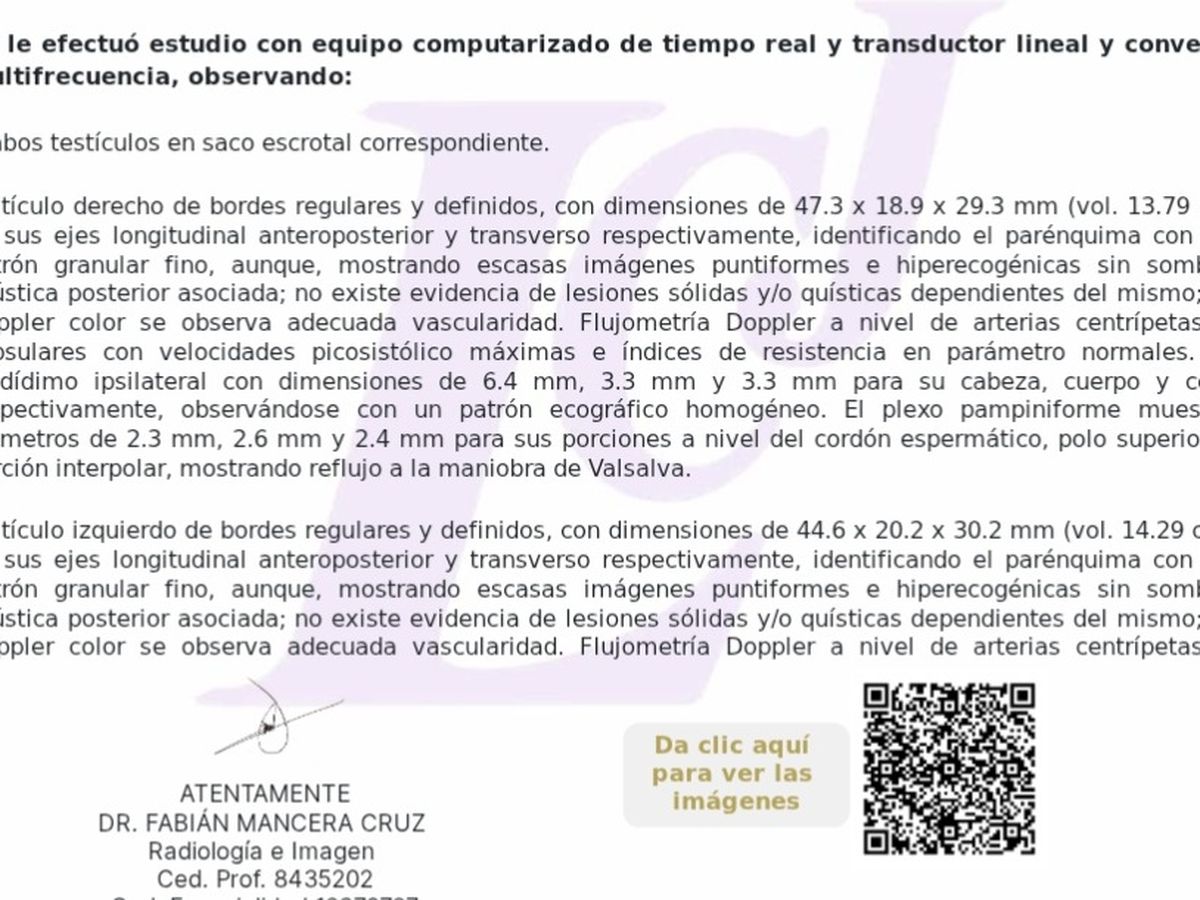

Hola me Llamo Raúl ,tengo 25 años , soy de la CDMX , me atrevo a pedir está ayuda , ya que desde hace unos meses empecé a sentir fuertes dolores en la zona de los testiculos, me hicieron estudios Doppler Testiculares, me detectaron Varicocele de Grado 4 en ambos testículos y microlitiasis testicular en ambos testículos y también tengo hernias en ambos conductos de los testiculos, sufro de fuertes dolores en ambos testículos , eso también está provocando que mi próstata este inflamada, no puedo mantenerme mucho tiempo parado o sentado, me duele mucho al orinar aveces con sangrado, llega el punto en que no puedo ya controlar la orina sale por su cuenta propia, no me atiendo en el IMSS porque el tiempo de espera es mucho , fui a médico particular y me dijeron que ya era urgente la operación porque la sangre no está llegando a los testiculos y se están muriendo, en estos momentos corro riesgo de Esterilidad , y las hernias si no se tratan pueden abrir mas y provocar que los intentos bajen por los conductos de los testiculos y sea una urgencia muy grava y riesgo de una extirpación del intestino si eso llega a pasar , pido su ayuda para poder llegar a esta cantidad, ya que en mi situación es muy difícil poder conseguir todo el dinero.